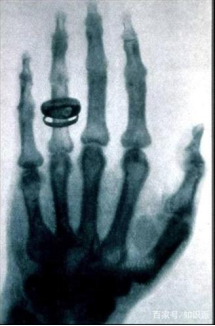

7.X射线

1895年11月8日傍晚,威廉·伦琴用阴极射线进行了一项实验。为了防止外界光线对放电管的影响,他把房间全部弄黑。可是当他切断电源后,却意外地发现一米以外的一荧光屏有闪光,而这绝非阴极射线造成的,经过反复实验,他确信这是种尚未为人所知的新射线,便取名为X射线。